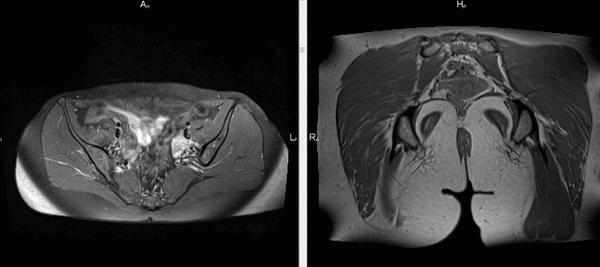

Магнитно-резонансная томография тазового пояса

Рыхлые структуры ягодичной области исследуют при возникновении:

выраженных болей в нижней части спины;

парестезии в зоне поясницы, крестца, ног;

застойных явлений, нарушений кровообращения в области малого таза и ягодиц.